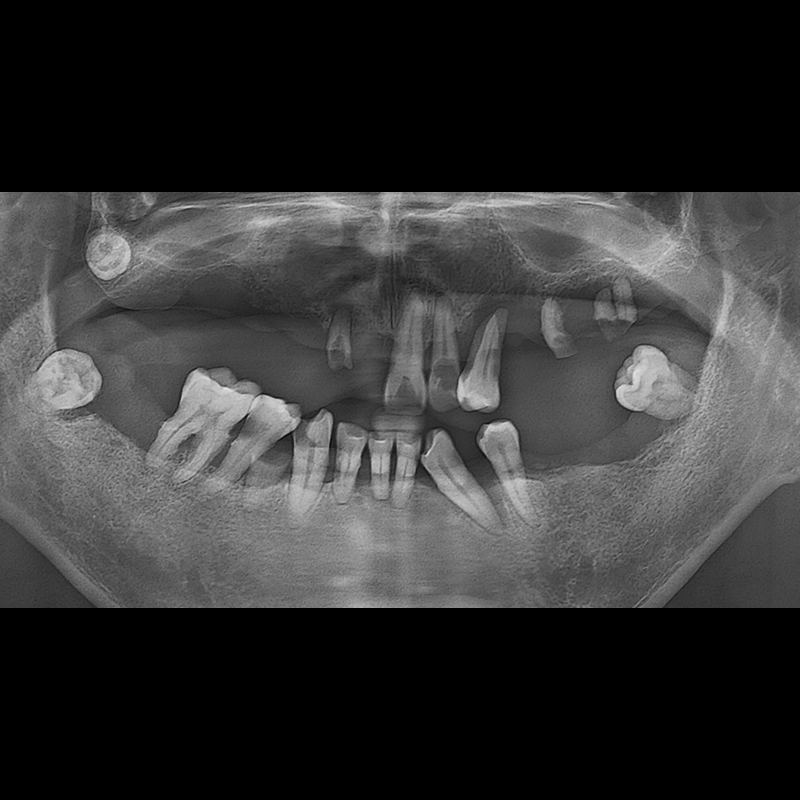

BEFORE AFTER

种植牙前后的照片 2025.05.30

在缺失的牙齿部分和难以挽救的牙齿位置植入了种植牙。